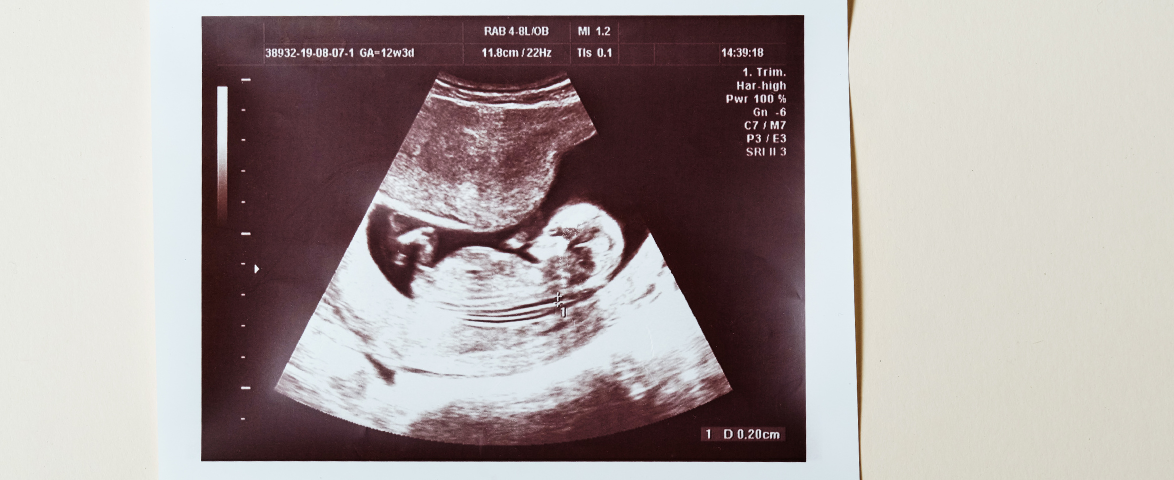

A Genetic Sonogram is an advanced ultrasound procedure recommended when the risk of Down Syndrome is suspected during pregnancy. This test provides a detailed evaluation of the fetus, helping doctors assess genetic health and plan the right medical care for the mother and baby.

A genetic sonogram is carried out when the Down Syndrome ultrasound screening  shows increased risk. During this test, specific fetal characteristics are closely examined through ultrasound imaging. These markers help doctors determine whether the risk of Down Syndrome is higher or lower.

During a Genetic Sonogram , the following ultrasound markers are carefully analyzed:

• Nasal bone development

• Nuchal fold thickness

• Aberrant Right Subclavian Artery

• Minor ventriculomegaly

By studying these signs, fetal medicine experts can provide an updated evaluation of the baby’s genetic health.